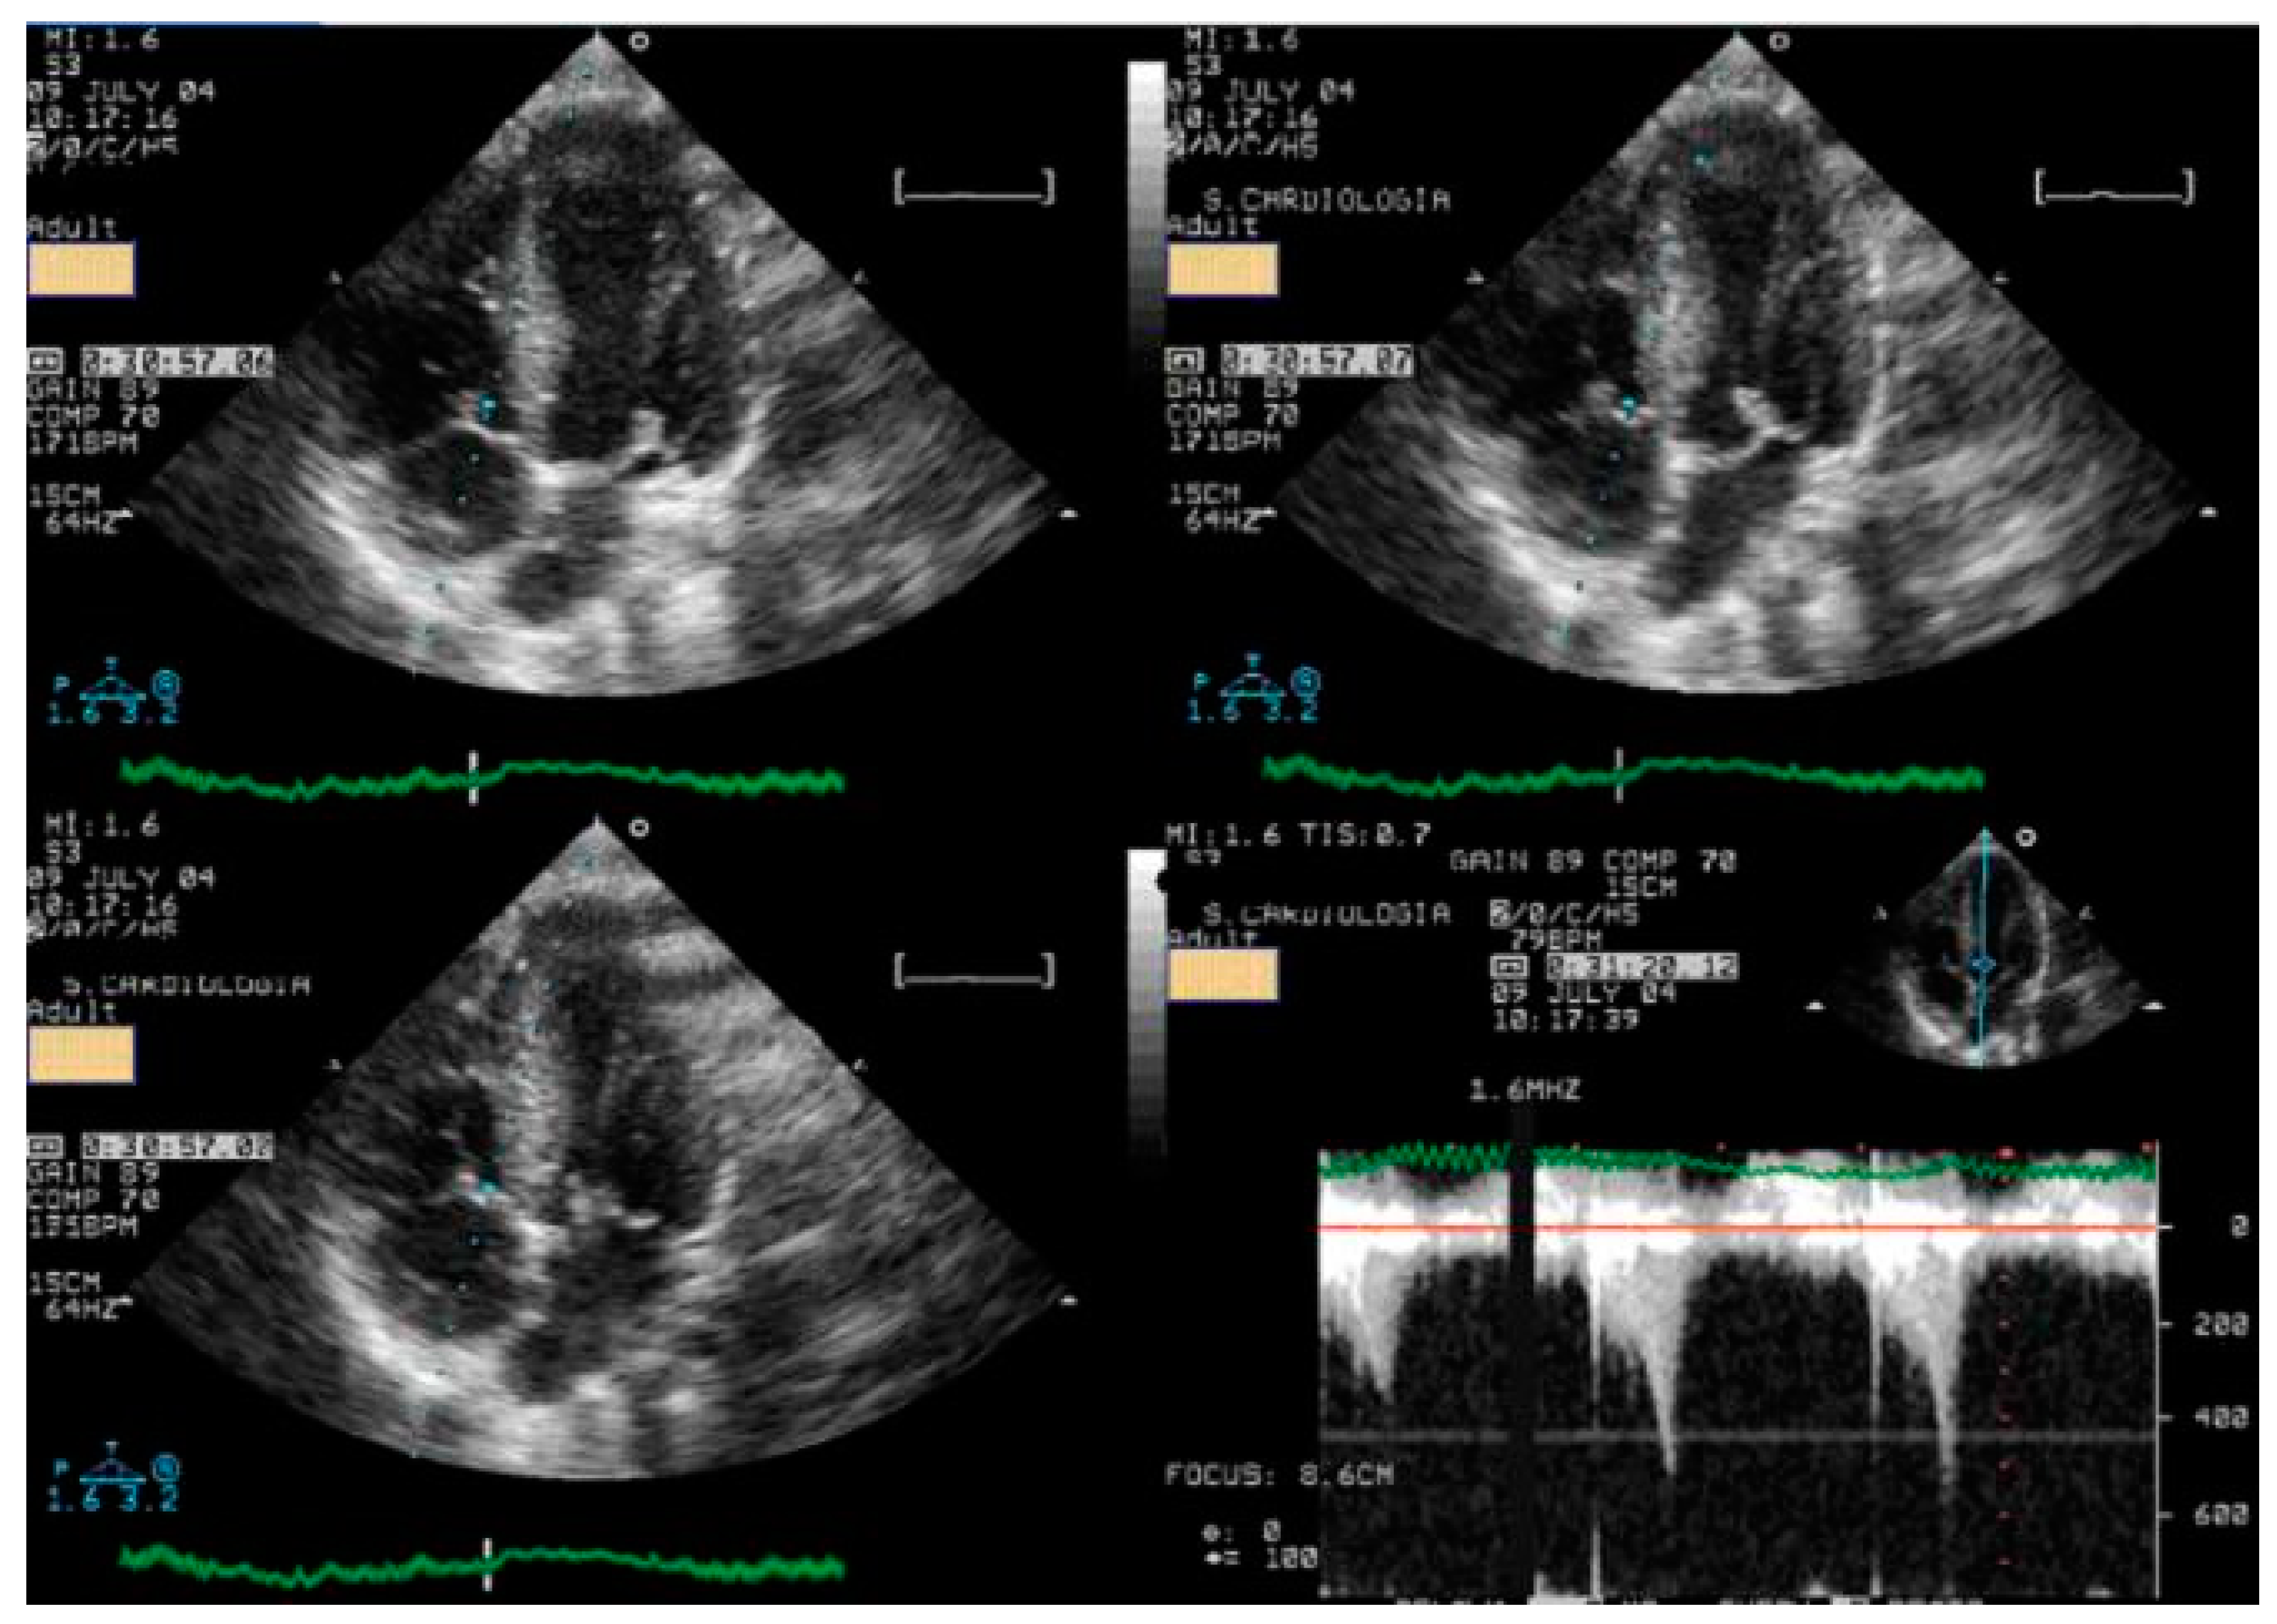

In Group II, the ten children with a diagnosis of HCM were non-obstructive before exercise, and four developed intraventricular obstruction with exercise. One of these four children is a symptomatic young boy whose exercise-induced obstruction was the first sign of HCM, having no hypertrophy at the moment of the ESE [24]. Another developed dilation of the left ventricle, particularly at the level of the apical segments (Figure 6).

Figure 6.

Intraventricular obstruction and contractility alterations during exercise in one symptomatic 16–year-old boy with obstructive hypertrophic cardiomyopathy.